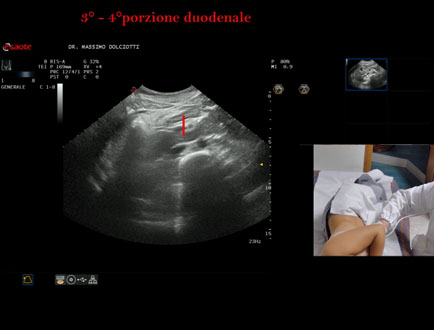

Data inserimento: 19/09/2025

Ecografia del: 10/09/2025

Strumento: Esaote MyLab Eight

Sonda: Convex Multifrequenza 1-8 MHz

Età Paziente: F 24 anni

Motivazione dell'esame:identificazione della terza e quarta porzione duodenale.

Commento all'esame: le immagini ed il video documentano il duodeno ed in particolare la terza e quarta porzione.

Conclusioni: 3° e 4° porzione duodenale (3rd and 4th duodenal portion).

Presentazione: Dr. Massimo Dolciotti - Ancona

Elaborazione digitale: Andrea Dini - Ancona